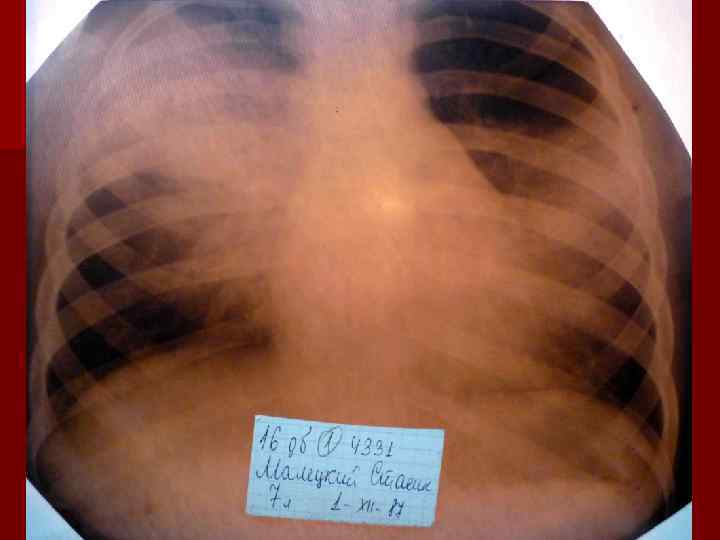

Долевая пневмония характеризуется лобарным пневмоническим инфильтратом. Крупозная ( пневмококковая) пневмония диагностируется прежде всего по клиническим данным. Крупозная пневмония сохраняет свою типичную картину пневмококковой пневмонии: острое начало с характерными клиническими данными, циклическое течение, несклонность к деструкции, гомогенной и лобарной инфильтративной тенью при рентгенологическом исследовании. Вместе с тем, широкое использование антибиотиков способствовало значительному снижению числа крупозных пневмоний у детей. Интерстициальная – редкая форма пневмоний, при которой оказывается поражен прежде всего интерстиций. Как правило, интерстициальная пневмония обусловлена вирусами, пневмоцистами, внутриклеточными микроорганизмами и грибами.

Морфологическую форму пневмонии определяют по клинико – рентгенологическим данным: выделяют очаговую, очагово – сливную, долевую ( крупозную), сегментарную и интерстициальную пневмонии. Очаговая – наиболее распространенная форма. Пневмонические очаги чаще бывают размером 1 см и более. Очагово – сливная – инфильтративные изменения в нескольких сегментах или во всей доле легкого, на фоне которых могут быть видны более плотные участки инфильтрации и/или полости деструкции. Сегментарная – в процесс вовлекается весь сегмент, который, как правило, находится в состоянии гиповентиляции, ателектаза. Морфологическая картина воспаления при очаговых и сегментарных пневмониях связана с первичным инфекционным воспалением в бронхах, что дает основание отнести эти варианты поражения легочной ткани к бронхопневмониям, нередко сопровождающихся бронхообструктивным или бронхообтурационным синдромами. В настоящее время данный тип пневмоний у детей встречается наиболее часто.